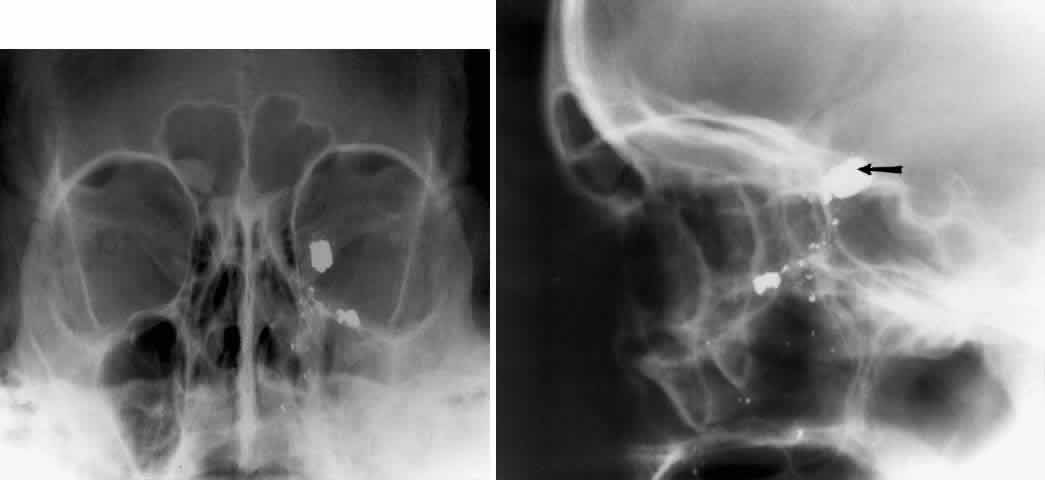

WATERS PROJECTION

In an attempt to improve the visualization of the maxillary and ethmoid sinuses, in 1915 Waters and Waldron7 described a radiographic projection (Fig. 2) that eliminated the overlapping shadows of the dense petrous ridge of the temporal bone. Waters projection is created by placing the chin of the patient on the x-ray cassette with the canthomeatal line (the line that connects the lateral canthus and the external auditory meatus) at 37 degrees to 45 degrees.5,6 This orientation is accomplished if the nose of the patient is approximately 0.5 to 1.5 cm above the x-ray plate.7,8 A mnemonic is—the patient raises the chin up to sip water.

Fig. 2. A. Schematic showing positioning for a Waters projection. (CM, canthomeatal line; CR, central ray) B. Radiograph of a Waters projection. The petrous ridge lies below the maxillary sinus. (a, frontal sinus; b, medial orbital wall; c, innominate line; d, inferior orbital rim; e, orbital floor; f, maxillary antrum; g, superior orbital fissure; h, zygomatic-frontal suture; i, zygomatic arch) (A; Rao VM, Gonzalez CF: Plain film radiography and polytomography of the orbit. In Gonzalez CF, Becker MH, Flanagan JC [eds]: Diagnostic Imaging in Ophthalmology, pp 1–7. New York, Springer Verlag, 1986)

Waters view provides the best image of the maxillary antrum and good images of the orbital rim, orbital floor, zygomatic bones and arches, lesser wing of the sphenoid, and infraorbital foramen. This view is useful to the clinician in orbital floor fracture assessment because of the clear image of the orbital floor and the underlying maxillary sinus. The floor of the orbit should form a continuous radiographic line with the lateral wall of the orbit. Confusion can occur regarding the location of the orbital floor and its relationship to the orbital rim. The orbital floor is located inferior to the orbital rim not in the same plane, because of the orientation of the patient's head in Waters projection. A soft tissue density in the roof of the maxillary sinus or opacification of the floor of the sinus suggests an orbital floor disruption.